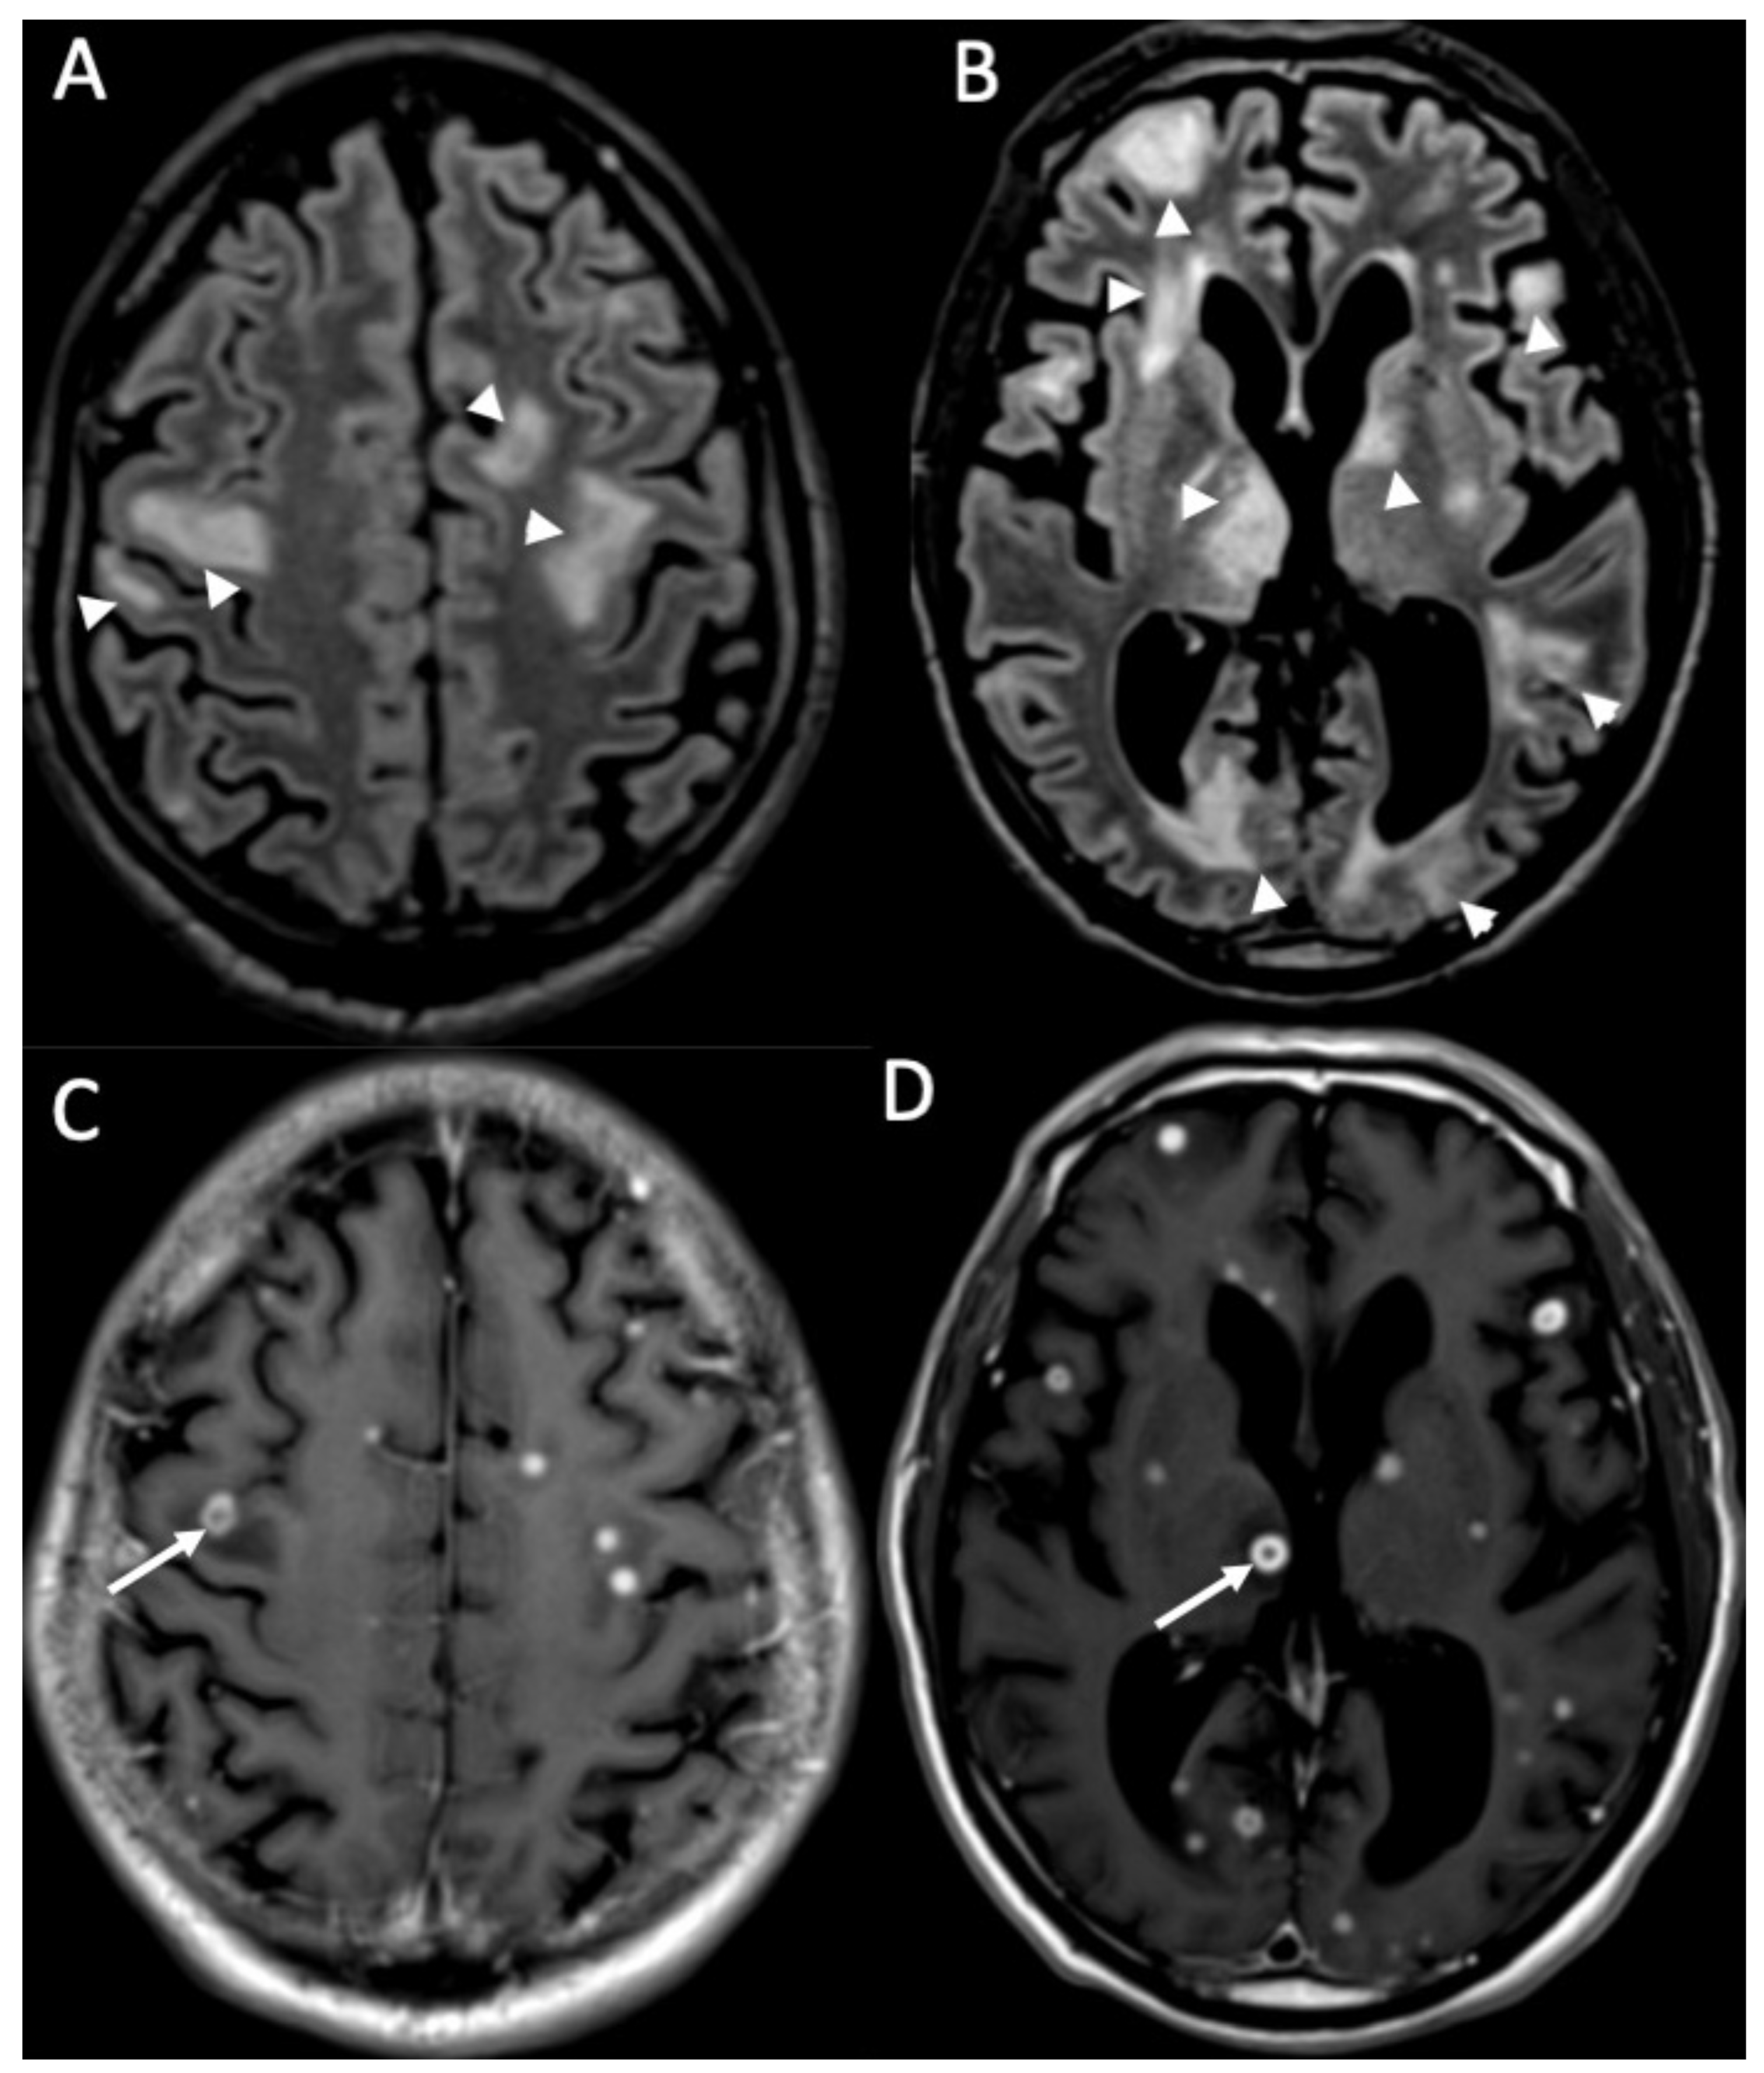

MRI with contrast injection is the imaging modality of choice, and the most common finding is leptomeningeal enhancement, which is present in almost 50% of patients [14]. Unenhanced T1 and FLAIR may show obliteration of basal cisterns and CSF hyperintensity related to increased protein content (Figure 1) [15]. Diffusion-weighted imaging (DWI) is important for detecting purulent material, which shows restricted diffusion, and it is usually located in the subarachnoid spaces at the convexity (Figure 2) [16]. DWI can be the only positive sequence; thus, it should always be checked accurately [16]. Contrast-enhanced FLAIR is the most useful sequence, and it has proved to be more sensitive than contrast-enhanced T1 for the detection of meningeal enhancement, which can be pachimeningeal (Figure 3) or (more frequently) leptomeningeal (Figure 4) [17]. Thus, it is recommended to add this sequence to the imaging protocol in every suspected case of meningitis. Enhanced T1 may show hypervascularity even in the absence of meningeal enhancement, especially in the first phase of the disease (Figure 2) [18].

Figure 1.

Axial FLAIR (A), T1 (B), coronal (C), and sagittal FLAIR (D) show diffuse hyperintensity on FLAIR and T1 of the subarachnoid spaces mainly in the cerebral convexity (arrows in A,B) in a patient with Streptococcus Pneumoniae meningitis. Note also concomitant cerebellitis, which appears as diffuse cortical hyperintensity on FLAIR of the cerebellum (arrowheads in C,D), with herniation of the cerebellar tonsils (arrow in D).

Figure 2.

Axial DWI (A), ADC (B) shows multiple foci of restricted diffusion in the subarachnoid spaces at convexity bilaterally (arrows in A,B) in a patient with newly diagnosed Streptococcus Pneumoniae meningitis.

Figure 3.

Axial DWI (A,E), FLAIR (B), enhanced FLAIR (C,D), show multiple recent ischemic areas (arrowheads in A,B,D) in a patient with Neisserria Meningitidis infection. Note also pachymeningeal (arrows in C) and leptomeningeal enhancement (arrows D) and purulent material in the subarachnoid spaces in the left insular region (arrowhead in E) and in the lateral ventricle bilaterally (arrows in E).

Figure 4.

Axial FLAIR (A), T2 (B), DWI (C), ADC (D), enhanced T1 (E), and FLAIR (F) of a patient with Streptococcus Pneumoniae depict multiple recent ischemic areas in the white matter in the fronto-parietal regions bilaterally (arrows in A–E), which are hyperintense on FLAIR and T2, show restricted diffusion and faint contrast enhancement. There is also a leptomeningeal enhancement in the right frontal and parietal regions (arrowheads in E,F). Note also a gliotic area in the right frontal region (*) due to a known previous ischemic event.